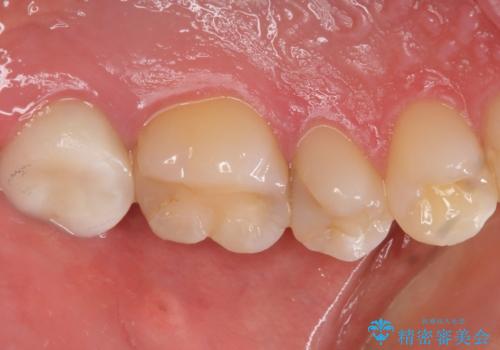

精査したところ、ほとんどの歯が保険内のレジンで充填されており、咬み合わせも悪く咬合していない歯もありました。

虫歯をしっかりと治療したのち、オールセラミッククラウンによる補綴治療を行いました。

クラウンの種類:オールセラミッククラウン スタンダード

シェード:NW0